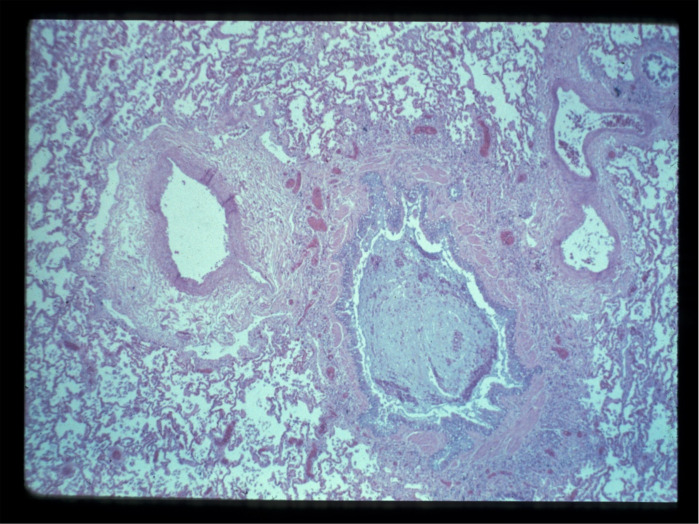

哮喘患者气道壁增厚,气道微血管参与气道壁的重塑。有假设,但没有令人信服的证据表明,重塑的气道血管在哮喘相关的气流阻塞中具有机械作用,有助于气道壁增厚和气道狭窄。本综述研究了支持和反对这一假设的文献,并提出了关于治疗哮喘患者直接靶向气道循环的问题。

The airway wall is thickened in asthma and the airway microvasculature participates in the remodelling. It has been assumed but not convincingly demonstrated that the remodelled airway vasculature has a mechanical role in asthma-associated airflow obstruction by contributing to the thickening of the airway wall and narrowing of the airway. This review examines the literature providing information in support of and against this assumption and raises questions about therapeutically targeting the airway circulation directly in patients with asthma.